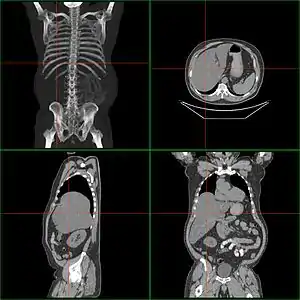

Computerized tomography of affected person with hepatomegaly

Computerized tomography (CT) can help to obtain accurate anatomical information, in individuals with hepatomegaly for the purpose of a complete diagnosis.[21]